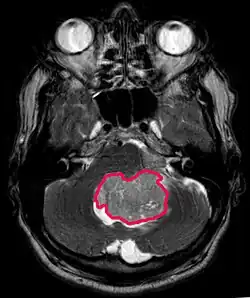

Este tumor é típico da fossa posterior, onde se localiza em ambos os hemisférios do cerebelo ou no vermis cerebelar. Por ser invasivo e de crescimento rápido, geralmente se espalha para outras partes do sistema nervoso central (SNC) através do LCR e pode se infiltrar no assoalho do quarto ventrículo próximo e nas meninges. Mais raramente, podem ocorrer metástases adicionais no SNC. Quando a malignidade ocorre, os sintomas incluem perda de equilíbrio, incoordenação, diplopia, disartria e devido ao envolvimento do quarto ventrículo, que muitas vezes resulta em hidrocefalia obstrutiva, cefaleia, náuseas e vômitos e marcha instável.

A ressonância magnética geralmente mostra uma lesão maciça com realce de contraste envolvendo o cerebelo. Como mencionado acima, o meduloblastoma tem alta propensão a infiltrar localmente as leptomeninges, bem como a se espalhar pelo espaço subaracnóideo, envolvendo os ventrículos, a convexidade cerebral e as superfícies leptomeníngeas da coluna. Consequentemente, é necessário trazer todo o eixo cranioespinhal em ressonância.

O objetivo da cirurgia é remover o máximo possível da massa apresentada pela lesão. De fato, os tumores residuais pós-operatórios resultam em pior prognóstico. Também um prenúncio de um prognóstico desfavorável é a presença de células tumorais no líquido cefalorraquidiano ou a detecção por ressonância de metástases leptomeníngeas. A cirurgia por si só geralmente não é curativa. Em alguns casos, no entanto, pode ocorrer irradiação terapêutica do eixo cranioespinhal, focada no local do tumor primário. A adição de quimioterapia após a radioterapia aumenta a taxa de cura. Medicamentos à base de platina (cisplatina ou carboplatina), etoposídeo e um agente alquilante (ciclofosfamida ou lomustina) são usados com vincristina. Com tratamento adequado, casos de longa sobrevida de mais de 3 anos em pacientes com meduloblastoma variam de 60 a 60 anos e 80 Por cento.